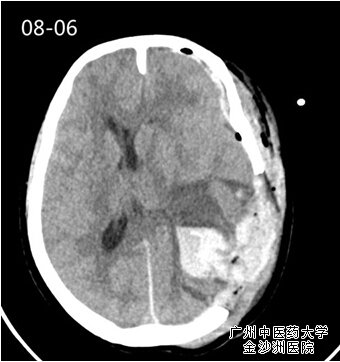

怎料一语成谶。病人术后回到病房不久,便出现对光反射消失,及“两慢一高” (血压增高,心率、呼吸变慢)脑疝症状,急查CT发现瘤腔远端左侧额颞硬膜下血肿,证实了周强教授术中所担忧,由于病人脑血管功能差导致手术区左侧远端桥静脉断裂出血,脑疝形成。“脑疝”是神经外科病房最不愿意听到的名词,它意味着死神的临近,脑疝的抢救成功与否可反应一个神经外科团队的综合能力;毋庸置疑,必需再次开颅清除血肿,否则病人性命难保。

8月5日15点~18点经过3小时麓战,清除颅内血肿、艰难细致的止血,手术成功,病人苏醒。让人始料未及的是,就在大家小憩之时,病人再次发生颅内出血、脑疝昏迷,惊险迭起如不及时手术将危及病人生命,于2015年8月6日再次手术颅内血肿清术,术后病人清醒,但很快病人又进入嗜睡状态,这意味着再次颅内出血,急诊复查头部CT证实颅内再次出血,而且病情极为凶险。院方立即组织广州市神经外科权威专家会诊,专家会诊一致意见“尽力抢救,但存活的可能性渺茫”;面对专家的会诊意见和家属绝望的恐慌,周强教授面对的社会压力以及家属可能不理解而出现的过极行为,决然未虑决定再次手术抢救,“只要有一线希望,都要百分之一百的努力”,这是他的行医准则。他耐心细致地和家属沟通,最终家属理解了只有再次手术亲人才有生存可能。

第一次术后血肿                                   第二次术后血肿